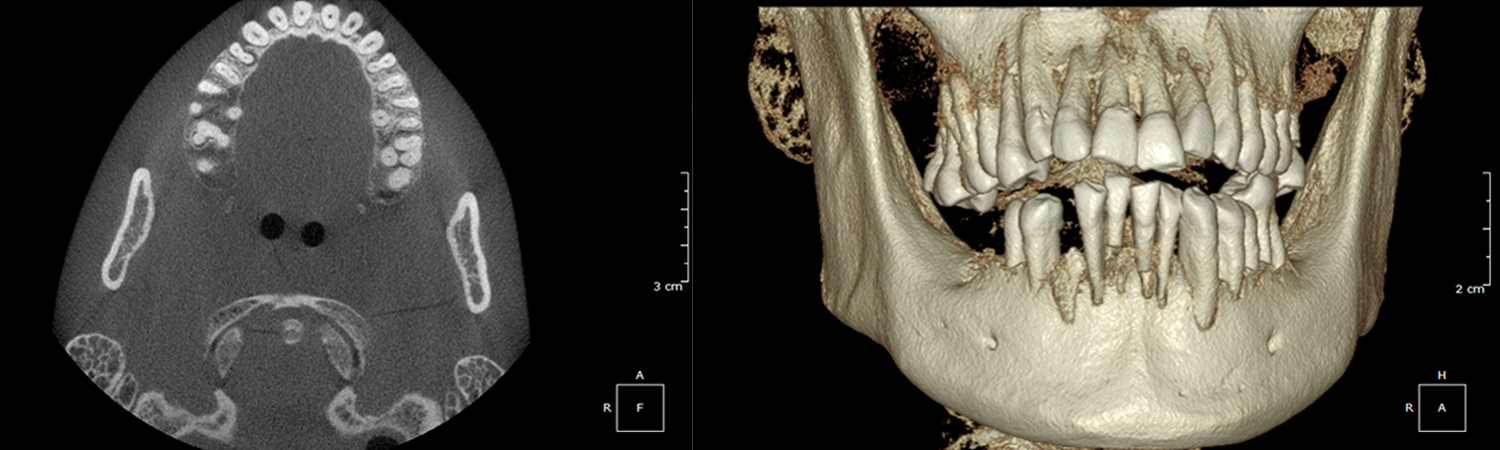

Undistorted, anatomically correct views of the jaws, teeth and facial bones along with cross-sectional (bucco-lingual), axial, coronal, sagittal, cephalometric and panoramic views are easily generated.